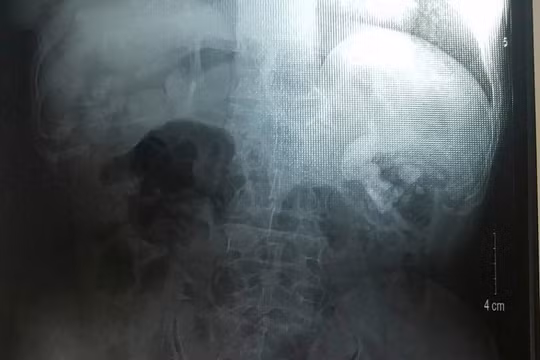

Nội soi êm ru “thổi bay” viên sỏi thận “khủng”

VietTimes -- So với cách thông thường là mổ mở hoặc cắt thận bán phần để lấy sỏi lớn ở đài bể thận, phương pháp nội soi qua da dưới định vị siêu âm sẽ giúp tán sỏi triệt để, mang lại hiệu quả vượt trội, giảm biến chứng nguy hiểm cho người bệnh